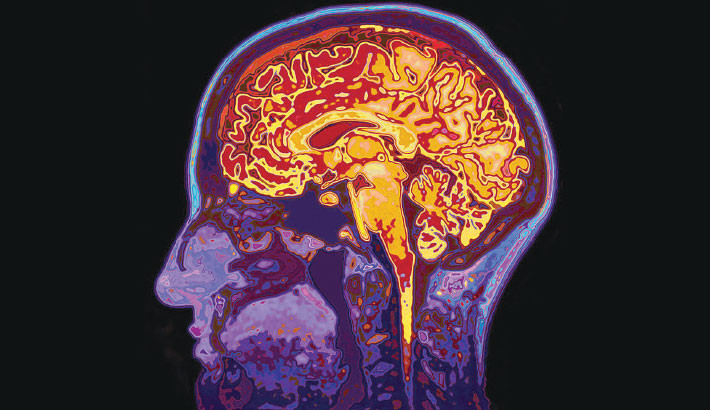

Middle-aged Brain Changes a Lot – and It Is Key to Understanding Dementia

Our brains change more rapidly at various times of our lives, as though life’s clock was ticking faster than usual. Childhood, adolescence and very old age are good examples of this. Yet for much of adulthood, the same clock seems to tick fairly regularly. One lap around the sun; one year older.

However, there may be a stage of life when the brain’s clock starts speeding up. The brain starts changing without you necessarily noticing it. It may even be caused (partly) by what’s in your blood. This stage of brain ageing during your 40s to 50s, or “middle-ageing”, may predict your future health.

This suggests that the brain may be going through accelerating, as opposed to gradual, change during this period. Several structures of the brain have been found to change in midlife. The hippocampus, an area critical for forming new memories, is one of them.

It shrinks throughout much of adulthood, and this shrinkage seems to accelerate around the time of middle age. Abrupt shifts in the size and function of the hippocampus during middle age could underlie memory changes like the ones mentioned above.

Ultimately, what allows the brain to carry out its functions are the connections between brain cells – the white matter. These connections mature slowly throughout adulthood, especially the ones connecting areas of the brain that deal with cognitive functions such as memory, reasoning and language.

Interestingly, during middle age, many of them go through a turning point, from gaining volume to losing volume. This means that signals and information cannot be transmitted as fast. Reaction time starts deteriorating around the same time.

Through the white matter connections, brain areas talk to one another and form interconnected networks that can perform cognitive and sensory functions, including memory or vision. While the sensory networks deteriorate gradually throughout adulthood, the cognitive networks start deteriorating faster during middle age, especially those involved in memory.